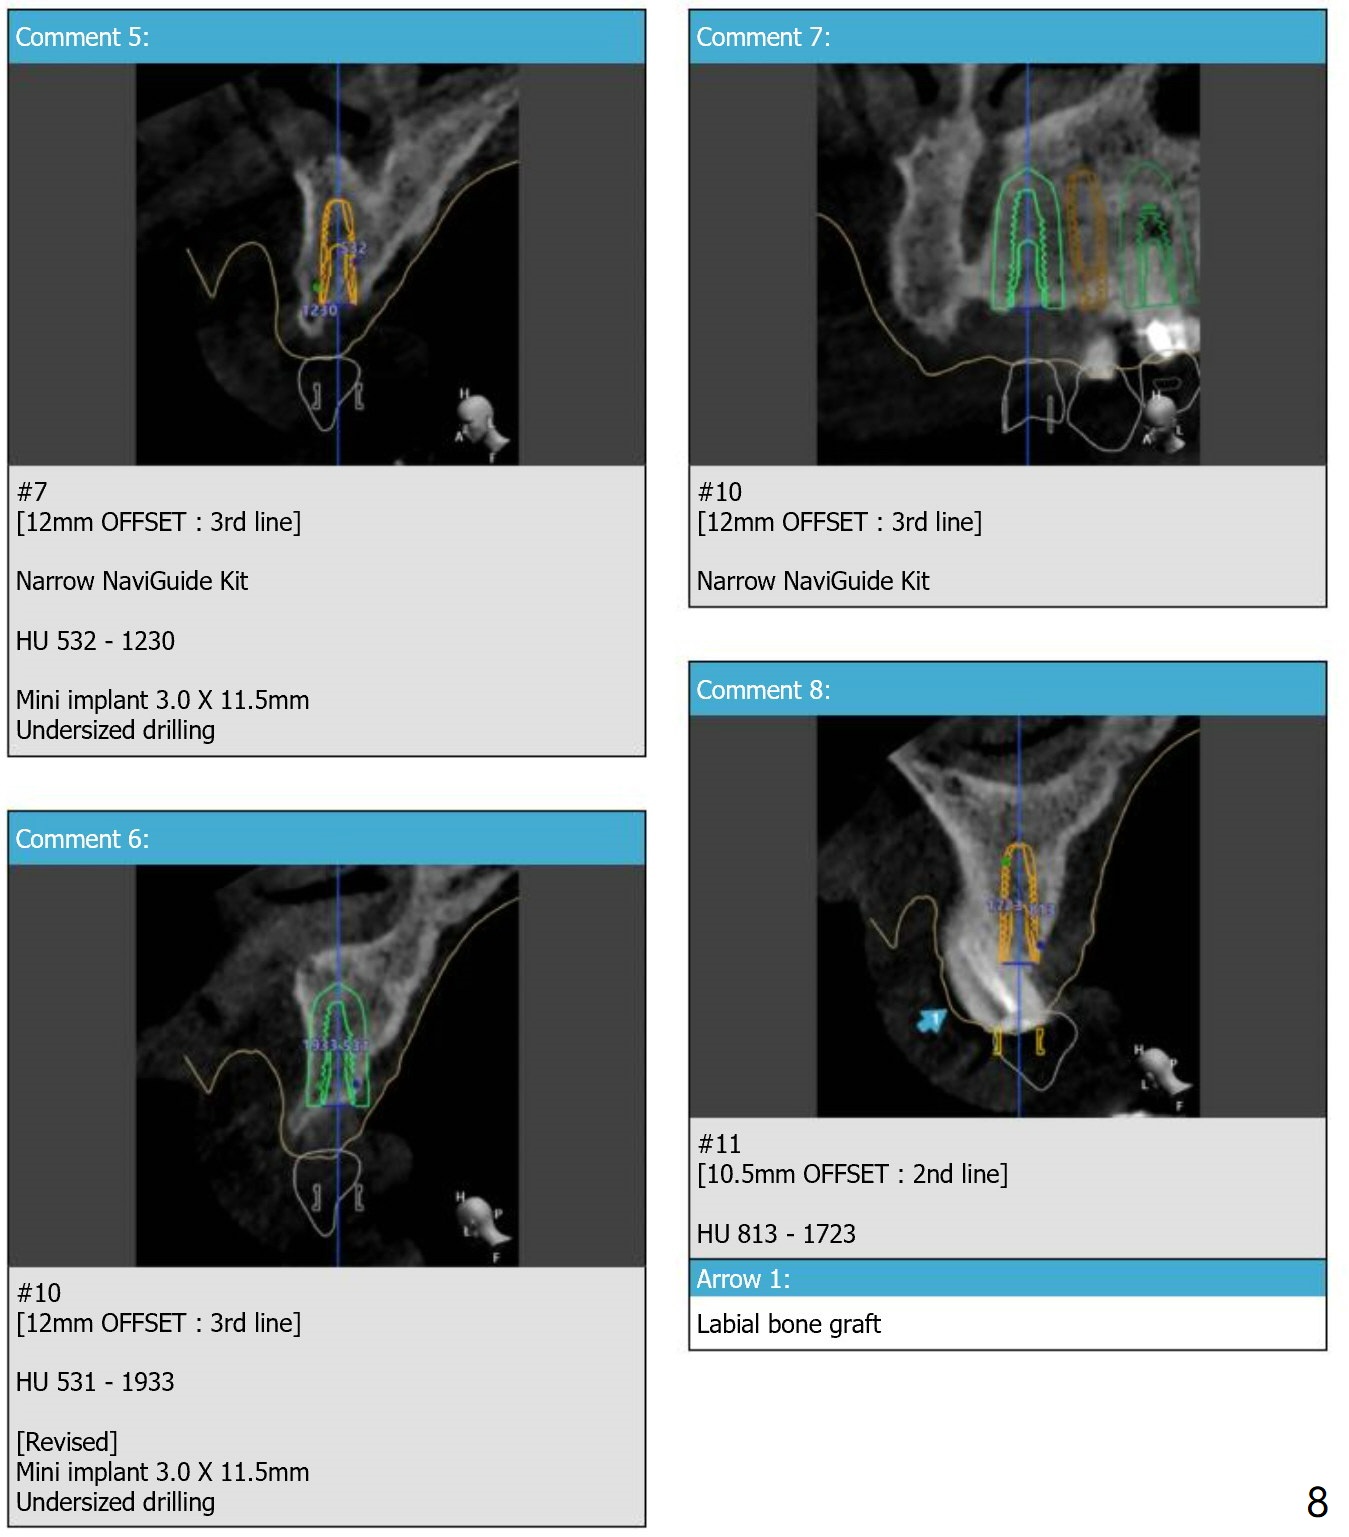

Since the apex of the tooth #5 seems to tilt mesial, implants at #6 and 7 will be placed mesial intentionally with diameters of 3.5 and 3 mm (Fig.1-3). On the left side with minor space issue, two-piece implants with 3.5 mm in diameter will be placed at #11-12 (Fig.5-6). After implant osteointegration, a 4-unit FPD will be fabricated between #7-10. Return to Upper Arch Immediate Implant, Trajectory, Metronidazole Xin Wei, DDS, PhD, MS 1st edition 11/09/2018, last revision 11/16/2018